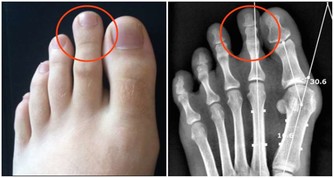

牙結石的出現主要是因為人的唾液中所含的礦物質,與口腔內的酸性分泌物發生反應,

產生了酸性化合物,它們很容易附著在牙齒背面,或牙齦與牙齒結合處,

刷牙不容易刷到,時間長了就變成頑固難除的牙結石。

牙結石會不斷刺激牙周組織,並會壓迫牙齦影響血液迴圈,

造成牙周組織的病菌感染,引起牙齦發炎萎縮,形成牙周囊袋。